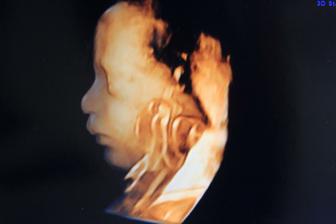

14.12.2010 dnes sme boli na morfologickom utz. ,všetko je v poriadku,len malinké sa akosi hambí,ešte aj nožičky prekrížilo. Pán dr. musel do neho štuchať lebo ani za nič na svete sa nechcelo otočiť a ukazoval nám ritku :°) Štuchal mi do bruška a malé sa len pomrvilo a to bolo všetko. Dr. povedal,že už od malička taký tvrdohlavý. A ručičky pred tváričku sa nás hambil. Aj 3D foto nám pán dr. dal :°) 20+2tt